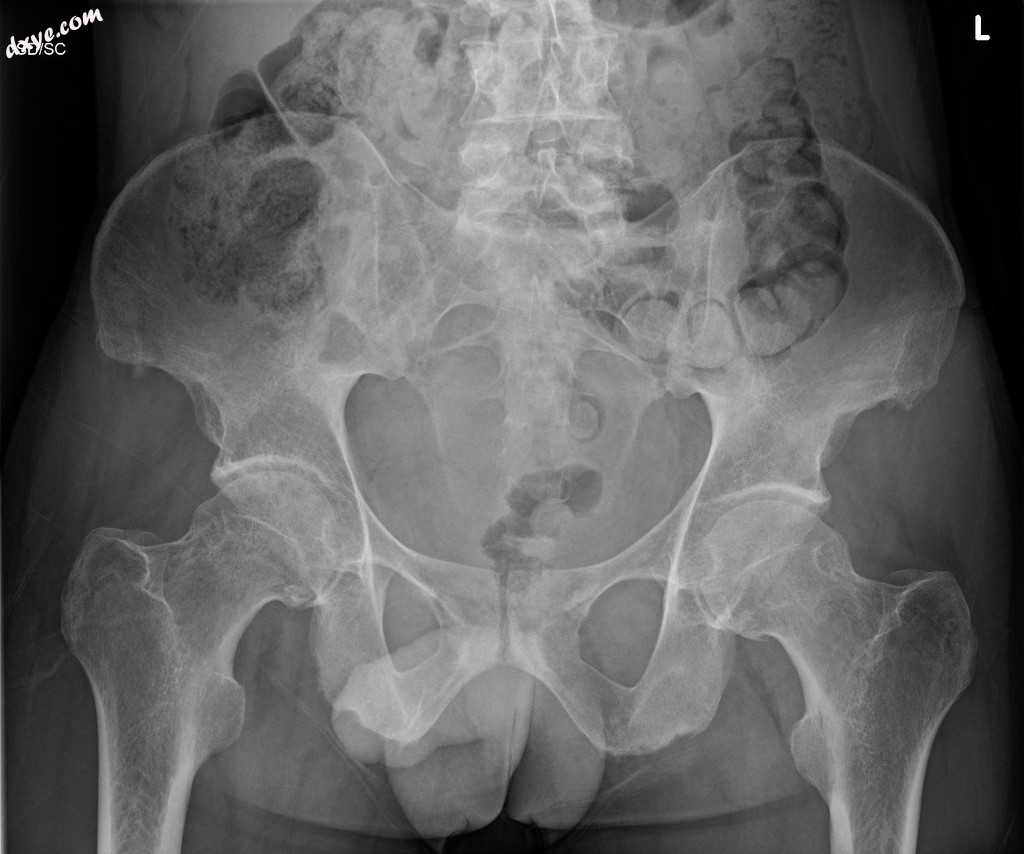

X线

正位

骶髂关节完全强直。

在已知的强直性脊柱炎患者中,骶髂关节完全强直是先前骶髂关节炎过程的末端。